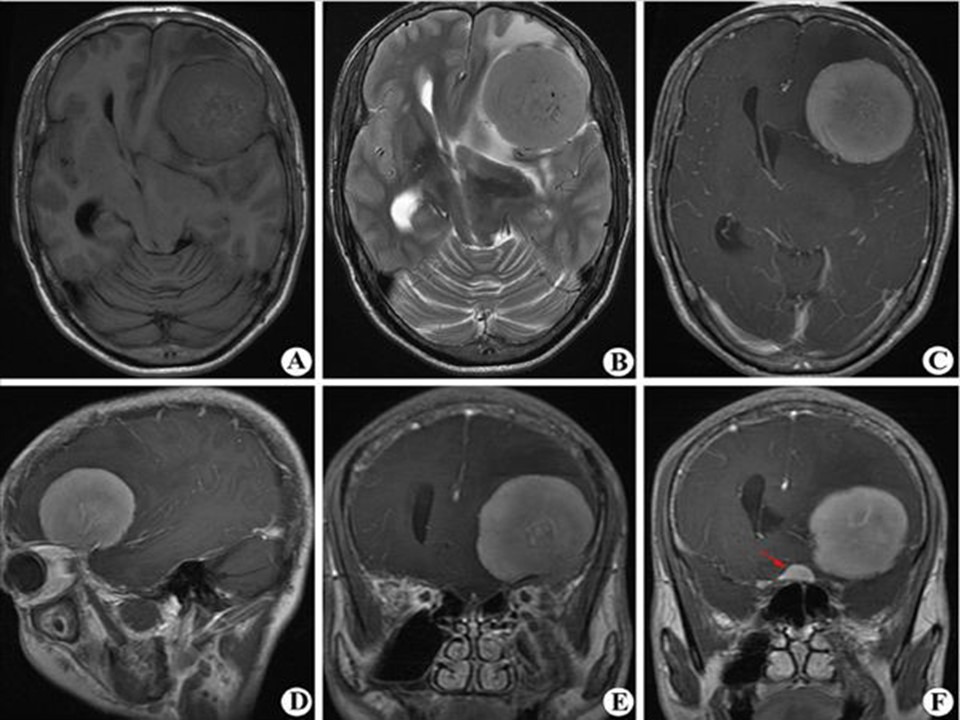

“头颅MRI入门PPT” 的相关文章